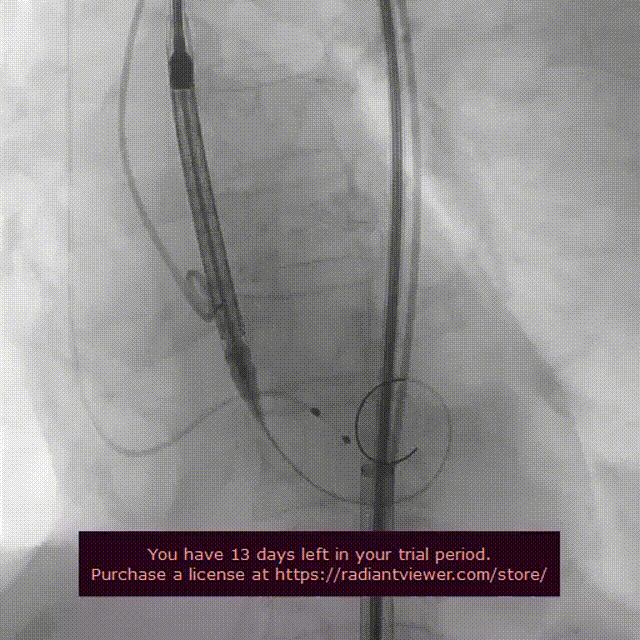

起搏150次/分,VenusA-Plus®L26标准位快速释放,释放至三分之二处,造影发现瓣膜位置不佳,下滑严重,快速进行回收,重新定位释放,造影发现第二次释放位置良好。

瓣膜位置下滑进行回收

瓣膜第二次释放造影